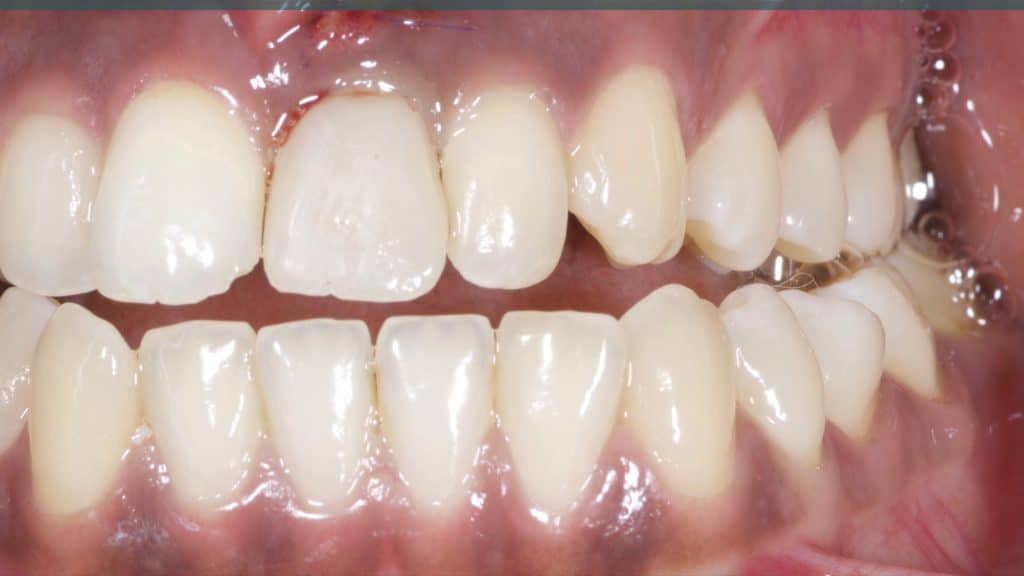

Occlusal check